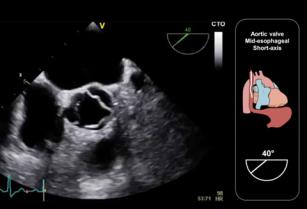

How to assess the left atrial appendage with the help of TEE 19th Sep 2017 - Andrew R. Houghton, MD Learn to obtain the left atrial appendage view in TEE & know what to look for to rule out a ...